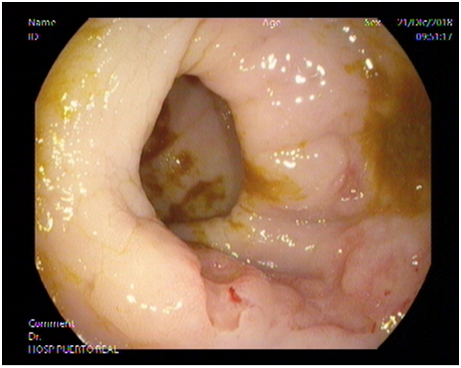

Subsequently, a colonoscopy was performed where, at the first Houston valve, an ulcerated lesion with a depressed center was identified, which appeared to extend around 1/3 of the circumference of the rectum, from which multiple biopsies were also taken. With the presumptive diagnosis of eventual disseminated rectal cancer in a patient with the known inflammatory disease, both samples were submitted for A.P study.

Figure 6 Diffuse non-Hodgkin lymphoma of large B cells of rectum in a patient with a history of ulcerative colitis on colonoscopic examination. (Pre-chemotherapy injury).

Figure 7 Diffuse non-Hodgkin lymphoma of large B cells of rectum in a patient with a history of ulcerative colitis on colonoscopic examination. (pre-chemotherapy injury).